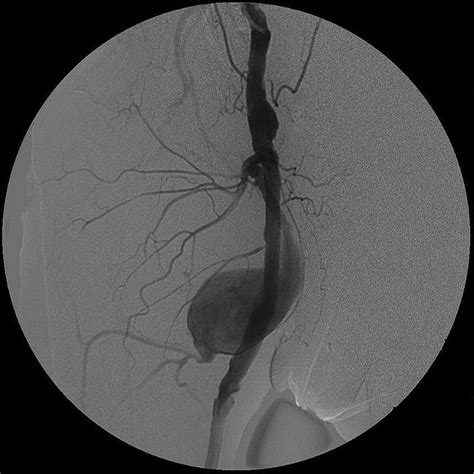

Physicians use various imaging techniques to confirm the presence of a femoral artery aneurysm and assess its size, location, and potential for complications. Accurate diagnosis is vital for planning the appropriate treatment path.

CT Angiography (CTA) Provides highly detailed cross-sectional images to map the vascular anatomy and plan for potential surgery.

When an aneurysm reaches a threshold size or begins causing clinical symptoms, surgical repair is usually advised. This is typically performed via open surgical bypass or, in select cases, endovascular repair. The goal is to restore normal blood flow and eliminate the risk of rupture or blockage.